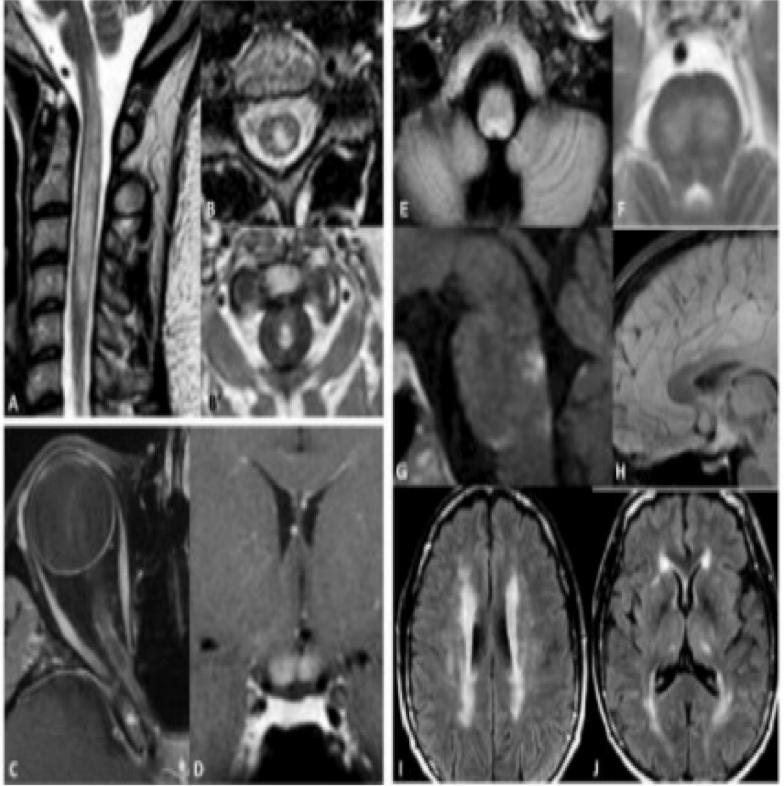

二、影像特征 1. NMOSD 脊髓MRI:长节段的脊髓炎(≥3个节段),呈中心分布,横贯性

2. NMOSD 视神经MRI:病变较长,累及视交叉

3. NMOSD 脑干MRI:四脑室周围,分布集中

4. NMOSD 头MRI:丘脑、三脑室周围、锥体束和侧脑室周围等部位都可能出现片状、云雾状病灶